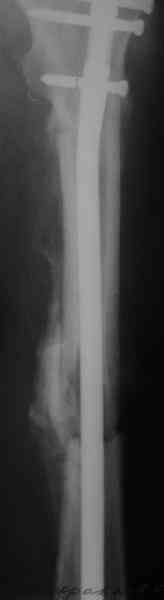

СМ> Если имеются под рукой Р-снимки, продемонстрируйте, плиз.

Вот несколько. С тисками и трубой на днях сделаем.

Гвозди с латерализованным проксимальным концом сейчас становится мэйнстримом, поскольку трохантерная точка входа во всех отношениях

благоприятнее f. piriformis.

Саша, последний штифт, пожалуй, перегнули?

> Саша, последний штифт, пожалуй перегнули?

Там заход сделан как для прямого штифта, не через вертел.